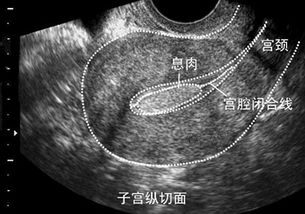

7、這兩種息肉癌變的幾率大嗎?我挺害怕的,病理結(jié)果要過兩天才出。

不大,拘報(bào)告是不到5%

病情分析: 你好,子宮內(nèi)膜息肉刮宮手術(shù)后該注意刮宮術(shù)后一定要預(yù)防感染治療,飲食上禁食生冷,辛辣刺激性食物,不要過度勞累. 多吃點(diǎn)富含營養(yǎng)的食物,因?yàn)橛胸氀梢赃m當(dāng)?shù)暮赛c(diǎn)豬肝湯補(bǔ)補(bǔ)血.你的子宮內(nèi)膜息肉建議做切除術(shù) 食補(bǔ)可以有:豬肝湯,桂圓蓮子湯,羊骨湯,阿膠等等.對于您問的手術(shù)后飲食上注意什么,手術(shù)后最好不要吃生蒜,辣椒,麻椒,鰻魚,咸魚,羊肉,蝦,蟹等,還要忌食生蔥,白酒等刺激性食物及飲料.另外有什么異常情況應(yīng)及時(shí)隨訪.以上就是我的回答,希望您可以滿意.。